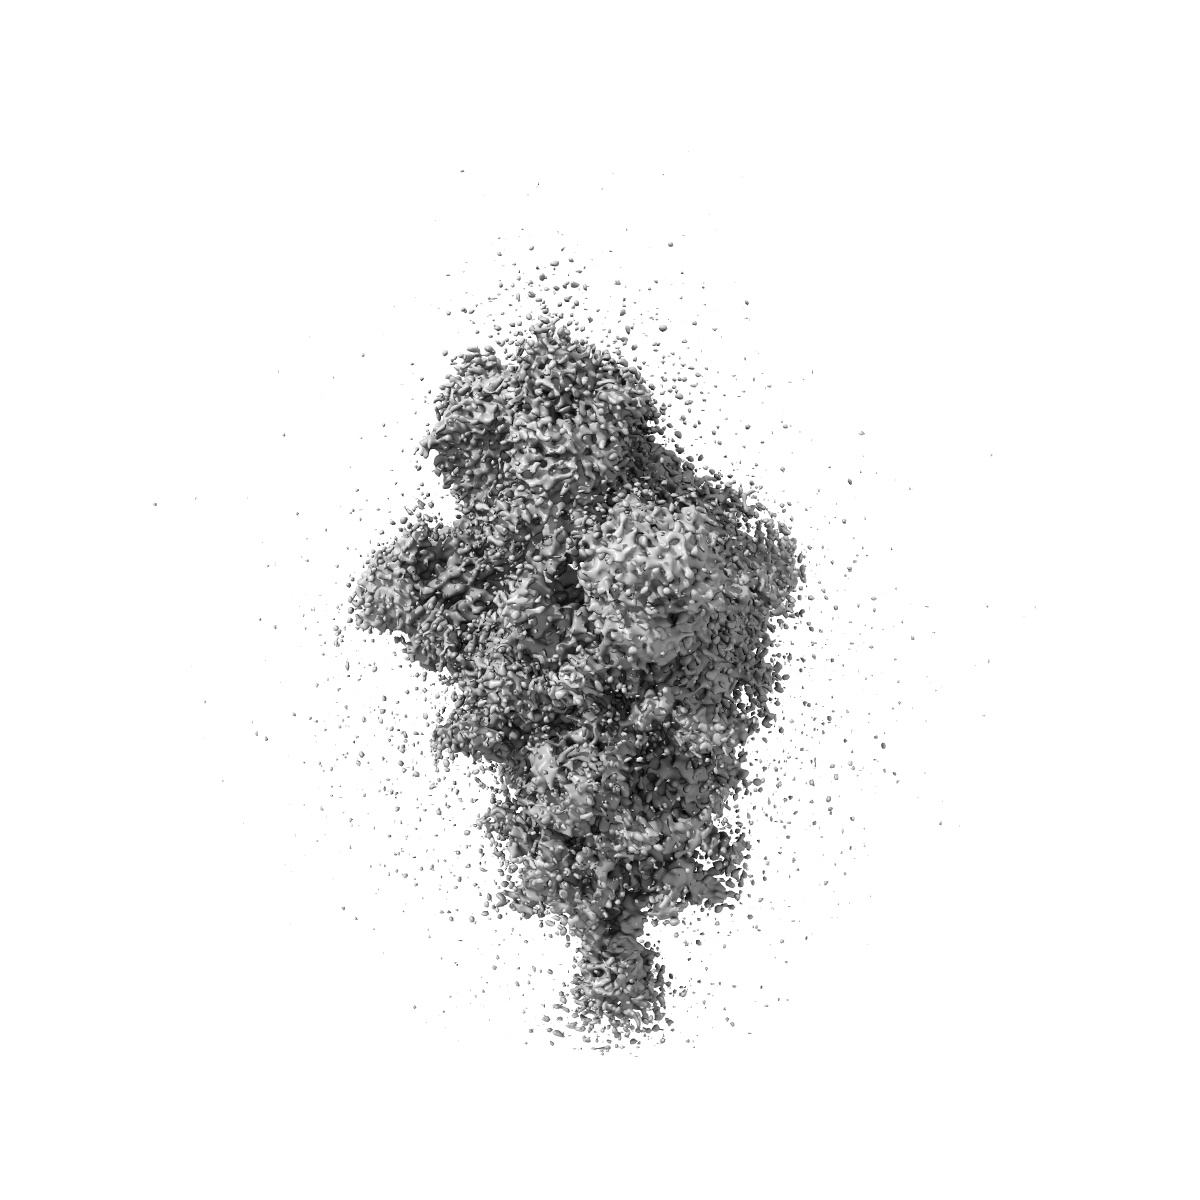

SARS-CoV-2 Spike protein in complex with the single chain fragment scFv76

Single-particle3.5 Å

Sample: SARS-CoV-2 Spike protein in complex with the single chain fragment scFv76